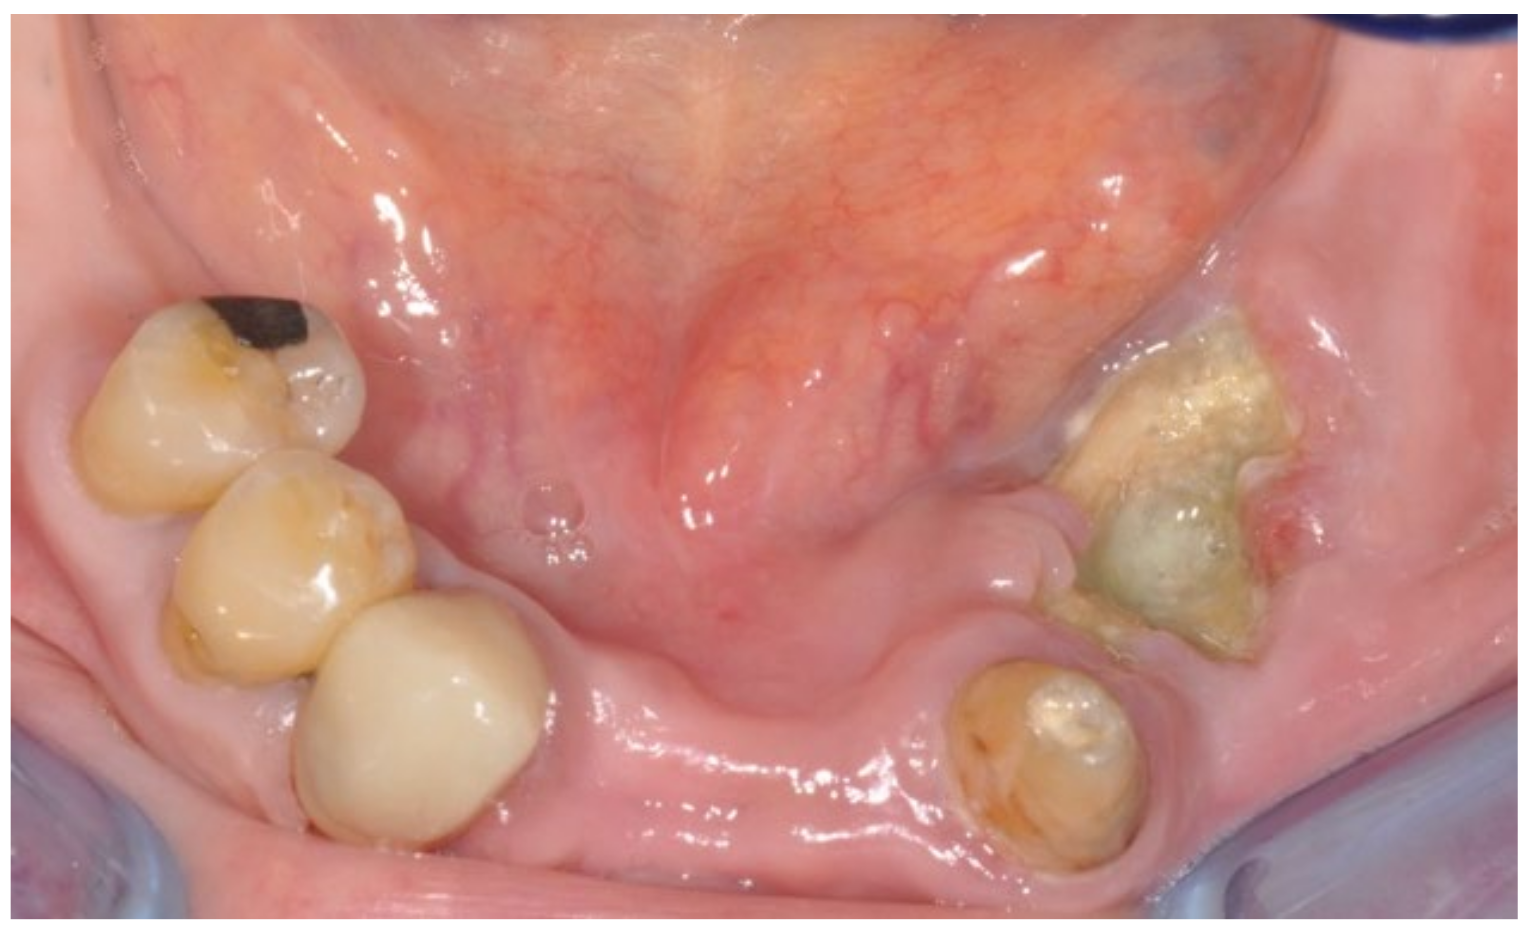

3.1. Clinical Case 1

3.2. Clinical Case 2

3.3. Clinical Case 3

3.4. Clinical Case 4

3.5. Clinical Case 5

3.6. Clinical Case 6